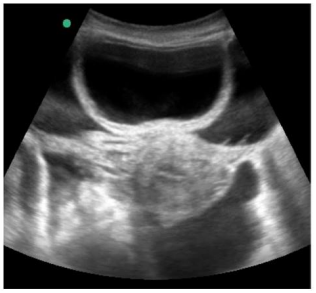

Um paciente de 76 anos de idade deu entrada na UPA, já fora de janela para trombólise, e foi posteriormente encaminhado para a UTI. A imagem apresentada refere-se à tomografia de admissão na UTI.

Com base na tomografia apresentada, assinale a alternativa que corresponde à artéria cerebral acometida e ao déficit esperado para o paciente

Na UTI, o paciente evoluiu com aumento progressivo dos níveis pressóricos e com bradicardia. Qual seria o exame mais facilmente disponível nesse momento, para tentar estabelecer um diagnóstico?

Diagnosticada a hipertensão intracraniana, a conduta mais prontamente adequada seria o uso de